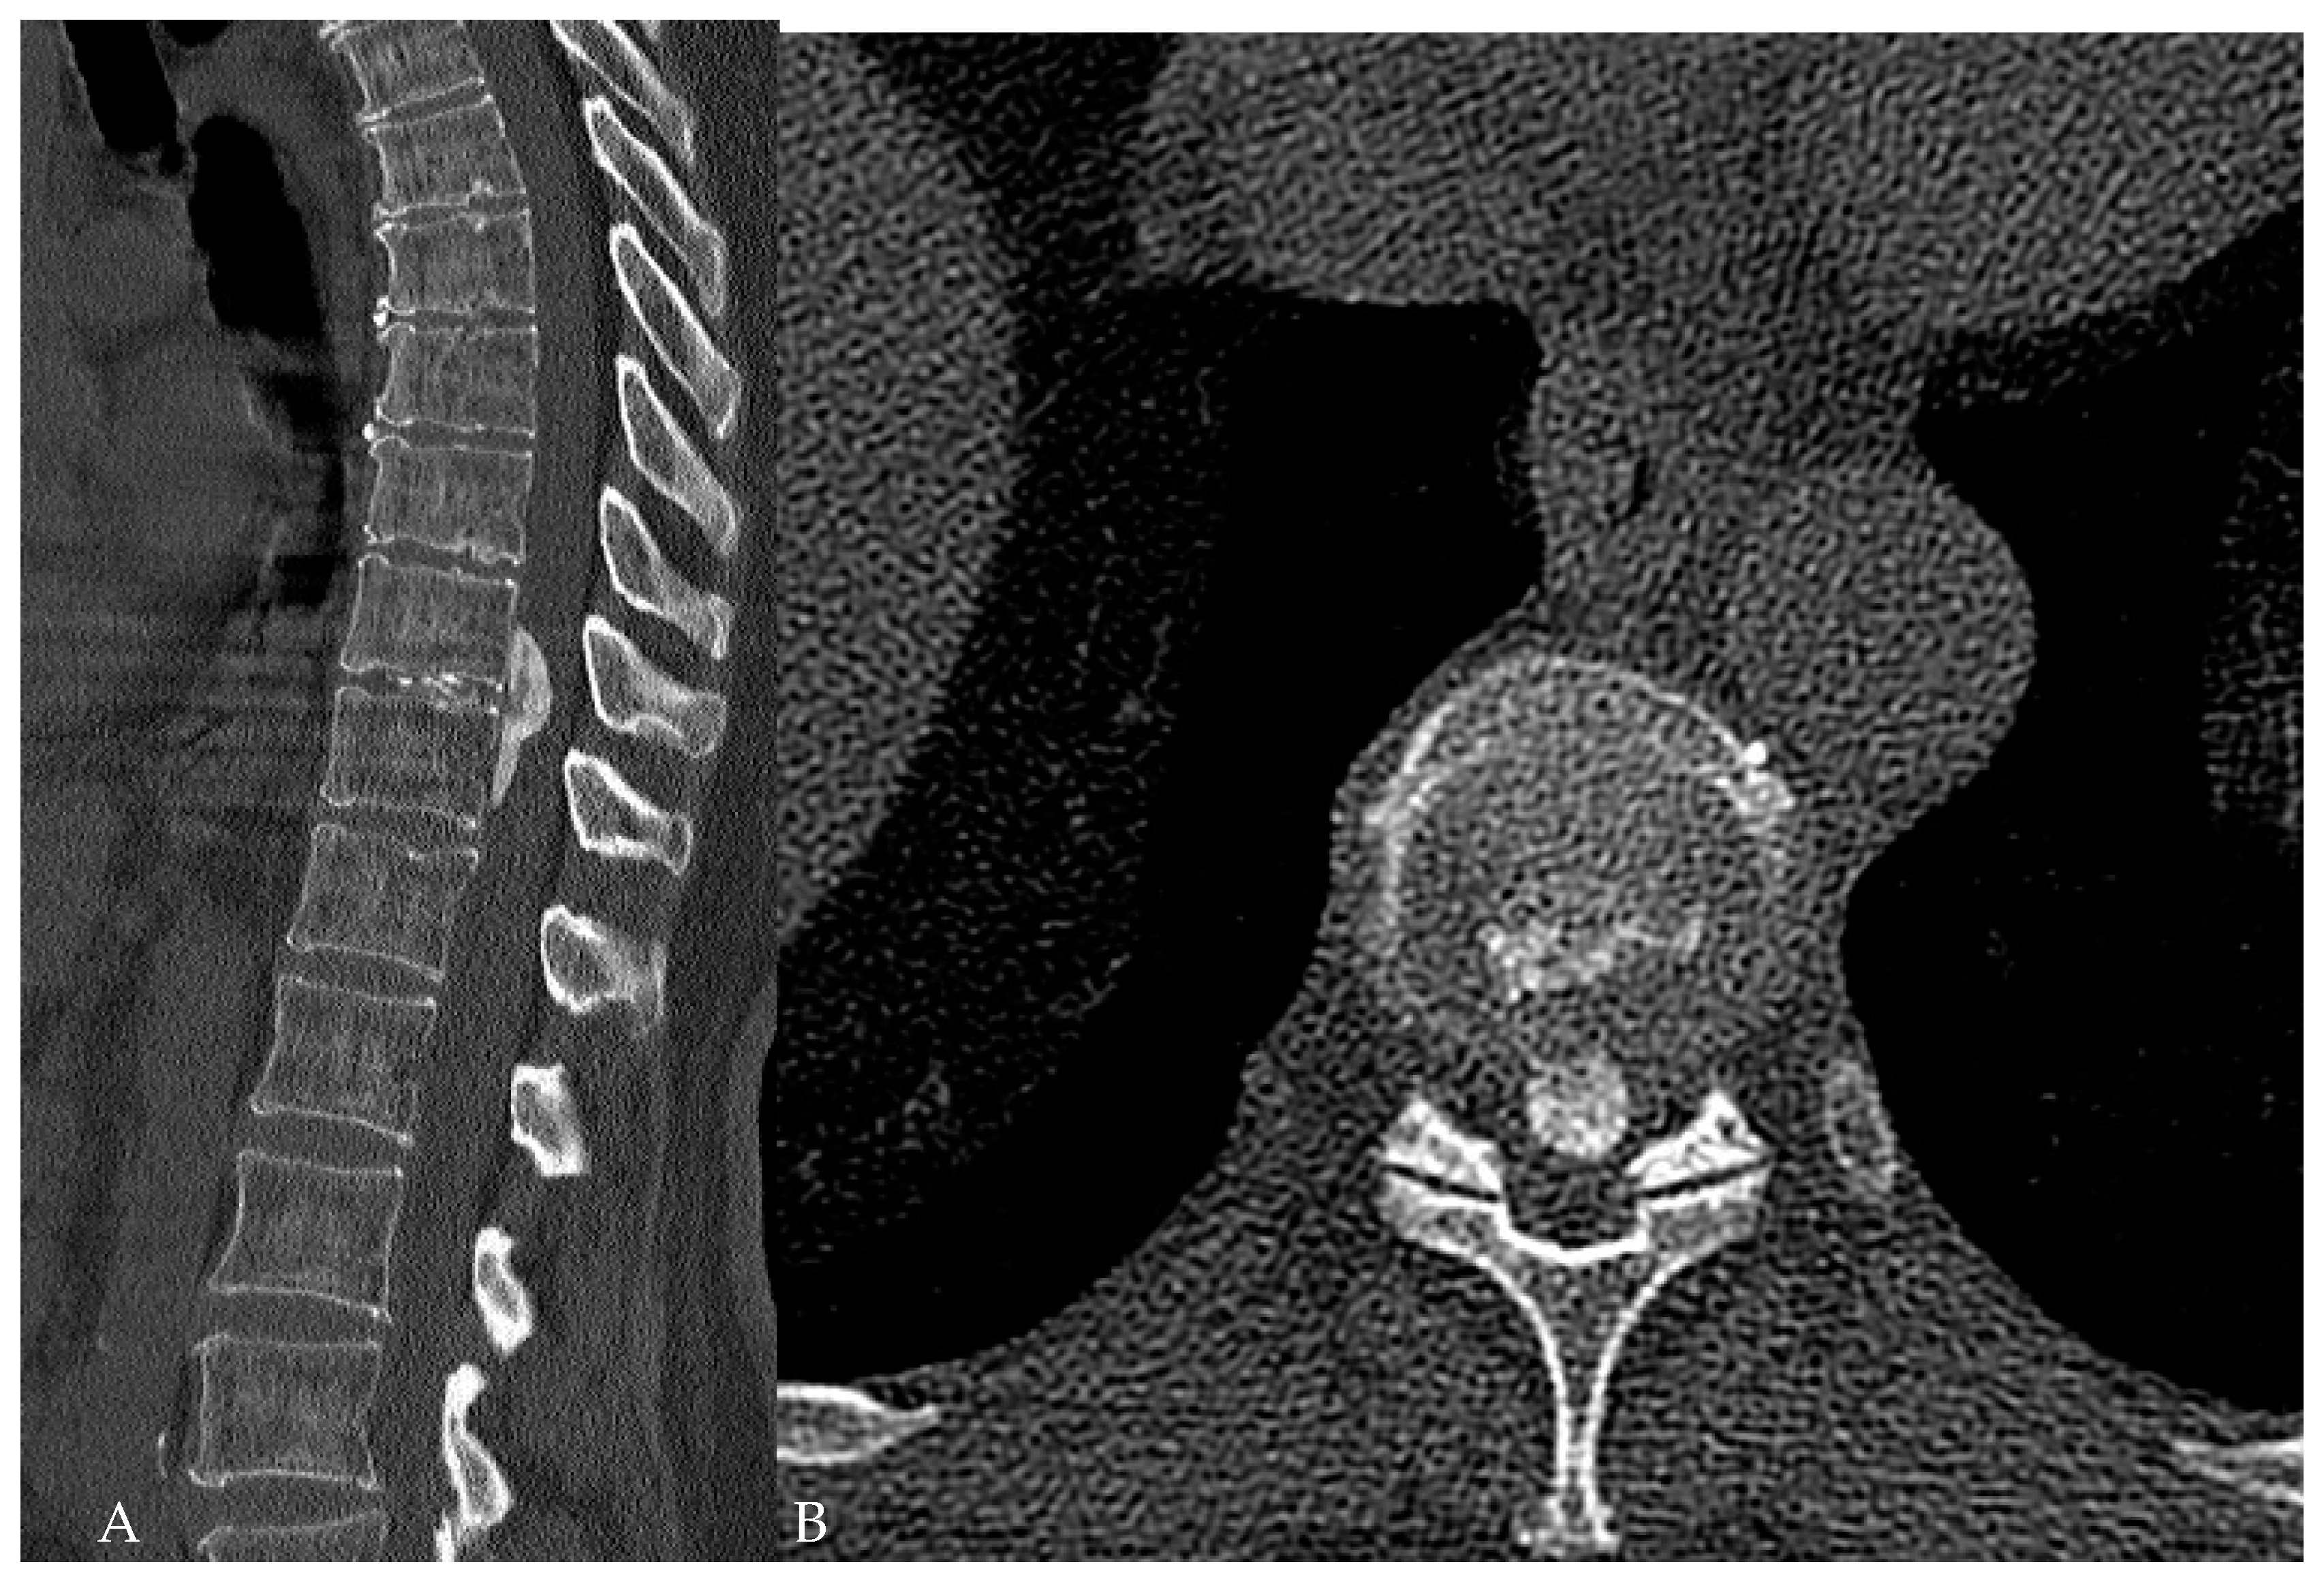

Surgical Treatment of Calcified Thoracic Herniated Disc Disease via the Transthoracic Approach with the Use of Intraoperative Computed Tomography (iCT) and Microscope-Based Augmented Reality (AR)

5.3. Use of Navigation and Intraoperative Imaging in the Resection of Herniated Thoracic Discs